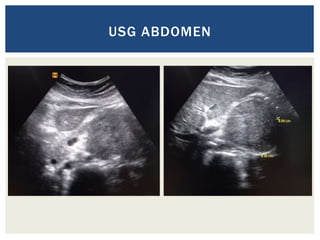

USG ABDOMEN

 A female patient of 30yrs of age

 Presented with complaints of vague abdominal discomfort for

last 3 months

 No other significant clinical or past history

 Clinical examination: WNL

CASE 1